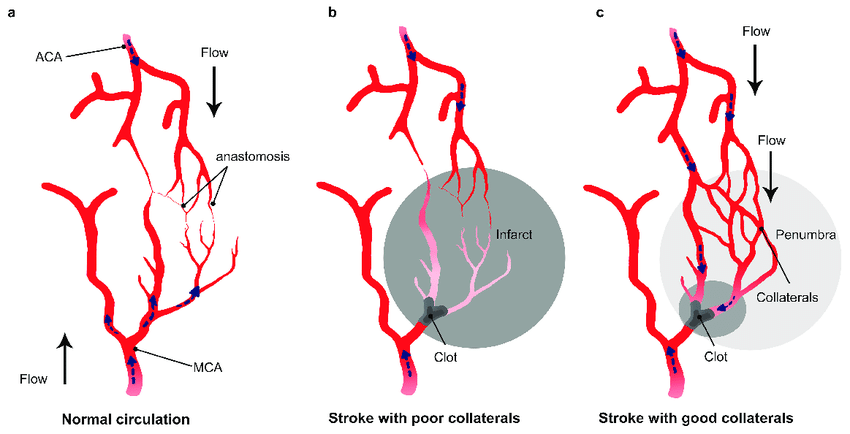

뇌는 담보 순환계를 통해 단일 동맥의 불충분한 혈류를 보상할 수 있다. 이 시스템은 경동맥과 척추동맥 사이의 효율적인 연결(주로 윌리스환을 통해, 그리고 다소 적은 정도로 대뇌반구에 혈액을 공급하는 주요 동맥을 통해)에 의존한다. 그러나 윌리스 환의 변이, 담보 혈관의 구경 및 죽상경화증과 같은 후천성 동맥 병변은 이러한 보상 메커니즘을 방해하여 동맥 폐쇄로 인한 뇌 허혈 위험을 증가시킬 수 있다.[70]

손상 정도는 허혈 지속 시간과 심각도에 따라 달라진다. 정상의 5% 미만으로 관류가 5분 이상 지속되면 일부 뉴런이 죽게 된다. 그러나 허혈이 경미한 경우 손상은 천천히 발생하며 뇌 조직을 완전히 파괴하는 데 최대 6시간이 걸릴 수 있다. 15~30분 이상 지속되는 심한 허혈의 경우, 영향을 받은 조직 전체가 죽어 뇌경색으로 이어진다. 손상 속도는 온도의 영향을 받는데, 고열은 손상을 가속화하고 저체온증은 손상 속도를 늦춘다. 허혈 조직에 대한 혈류의 신속한 회복은 특히 조직이 아직 돌이킬 수 없이 손상되지 않은 경우 손상을 줄이거나 되돌릴 수 있다. 이는 심한 허혈 부위 주변의 중등도 허혈 부위(반암영역)에 특히 중요한데, 이 부위는 담보 혈류 때문에 여전히 회복될 가능성이 있기 때문이다.[70][71][72]

허혈성 뇌졸중은 뇌의 일부로 가는 혈액 공급이 차단되어 발생하며, 허혈 연쇄 반응을 일으킨다.[65] 동맥경화증은 혈관 내강을 좁히거나 혈전을 형성하고, 작은 색전을 방출하여 혈액 공급을 방해한다.[66] 색전성 뇌경색은 심장이나 경동맥에서 형성된 색전이 뇌혈관을 막아 발생한다. 뇌혈관이 막히면 뇌는 에너지가 부족해져 혐기성 대사를 이용하게 되는데, 이는 아데노신 삼인산(ATP)을 적게 생성하고 젖산을 생성한다. 젖산은 뇌의 산-염기 균형을 방해하고 세포를 파괴할 수 있다. 허혈 영역은 "허혈성 반그늘"이라고 불린다.[67]

허혈은 활성산소 및 기타 활성산소종의 생성을 유도하여 세포 및 세포외 요소에 손상을 입힌다. 뇌는 담보 순환계를 통해 단일 동맥의 불충분한 혈류를 보상할 수 있지만, 윌리스환의 변이, 담보 혈관의 구경 및 동맥 병변은 이러한 보상 메커니즘을 방해할 수 있다.[70]

뇌에서 연막 측부 순환이 있는 경우 재관류 치료 후 임상 결과가 더 좋다.[78] 뇌혈관 저장 용량은 뇌졸중 결과에 영향을 미치는 또 다른 요인이다. 이는 의사가 이산화탄소 흡입 또는 정맥 아세타졸아마이드와 같이 혈류를 의도적으로 자극하여 혈류 증가량을 측정하는 것이다. 혈류 증가는 PET 스캔 또는 경두개 도플러 초음파로 측정할 수 있다.[79] 그러나 한쪽 내경동맥이 막힌 사람의 경우 연막 측부 순환이 있으면 대뇌 저장 용량이 감소한다.[80]